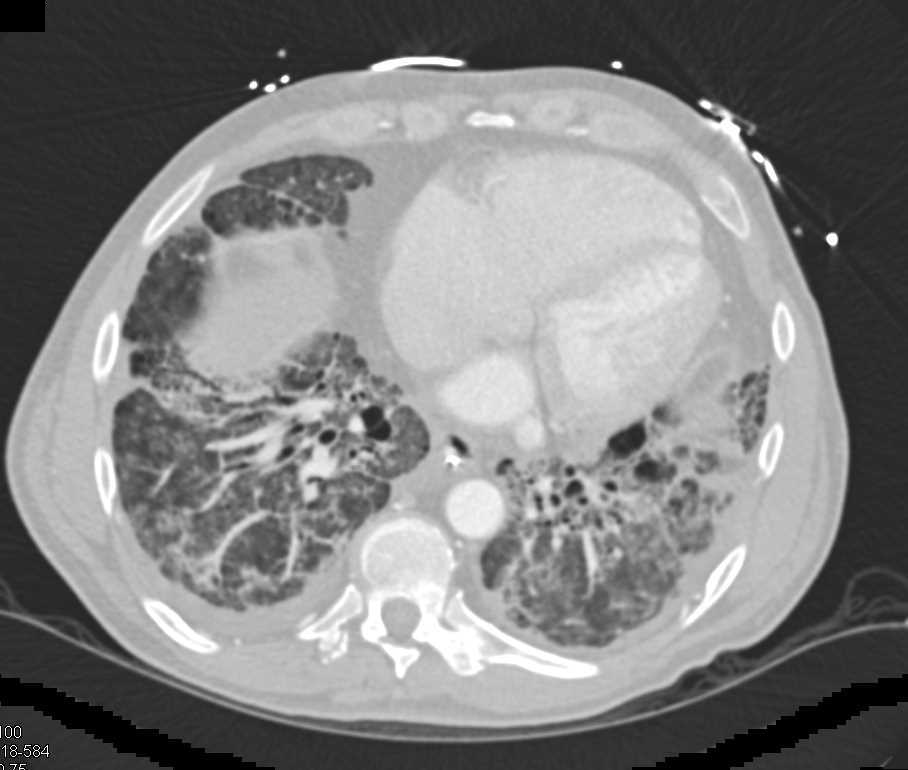

Interstitial Fibrosis Lung and Peripheral Vascular Disease